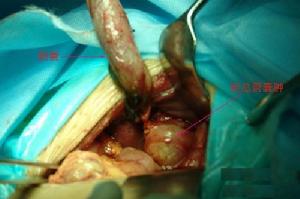

3.擴張膽總管、膽囊切除,胰膽分流、膽道重建術

自上世紀六十年代末國際上開始套用此術式,目前國內外學者已一致認為是治療本症首選的術式,可以解決囊腫、腸管吻合內引流手術所存在的許多問題。其優點為:①解決膽總管狹窄的問題。②可以較徹底地切除病灶,同時胰膽管的分流可以去除胰膽管合流異常的重要病理改變,防止胰液在囊腫內與膽汁合流。由此可以徹底解決由於囊腫內反流的胰酶導致被肝臟軛合解毒的致癌物質脫軛合而恢復其致癌性的問題,達到預防癌變發生的目的。③手術後併發症少,較囊腫腸管吻合引流手術的遠期療效明顯好。④可以通過近端的肝總管了解左右肝管,甚至肝內膽道的病變,予以必要的處理。⑤可以了解胰膽共同通道內可能存在的胰石等病變的問題,進行必要的處理。

擴張膽總管、膽囊切除、膽道重建術常用的術式有肝總管-空腸Roux-Y吻合,空腸間置、肝管-十二指腸吻合術、肝總管-十二指腸吻合及空腸間置代膽道加矩形瓣等附加的各種抗反流的分支術式。國內外都有報導經腹腔鏡行膽總管囊腫切除,肝管空腸Roux-Y吻合術,並取得較好的效果。